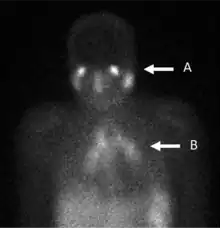

A gallium scan is a type of nuclear medicine test that uses either a gallium-67 (67Ga) or gallium-68 (68Ga) radiopharmaceutical to obtain images of a specific type of tissue, or disease state of tissue. Gallium salts like gallium citrate and gallium nitrate may be used. The form of salt is not important, since it is the freely dissolved gallium ion Ga3+ which is active.[1] Both 67Ga and 68Ga salts have similar uptake mechanisms.[2] Gallium can also be used in other forms, for example 68Ga-PSMA is used for cancer imaging. The gamma emission of gallium-67 is imaged by a gamma camera, while the positron emission of gallium-68 is imaged by positron emission tomography (PET).

Gallium salts are taken up by tumors, inflammation, and both acute and chronic infection,[3][4] allowing these pathological processes to be imaged. Gallium is particularly useful in imaging osteomyelitis that involves the spine, and in imaging older and chronic infections that may be the cause of a fever of unknown origin.[5][6]

In the past, the gallium scan was the gold standard for lymphoma staging, until it was replaced by positron emission tomography (PET) using fludeoxyglucose (FDG).[9][10] Gallium imaging is still used to image inflammation and chronic infections, and it still sometimes locates unsuspected tumors as it is taken up by many kinds of cancer cells in amounts that exceed those of normal tissues. Thus, an increased uptake of gallium-67 may indicate a new or old infection, an inflammatory focus from any cause, or a cancerous tumor.